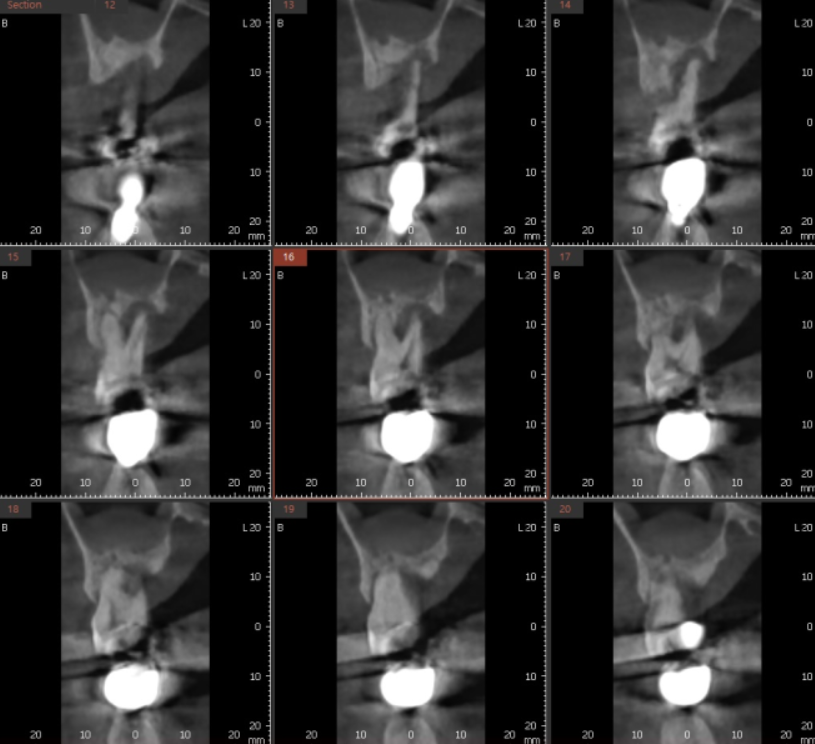

뼈가 적당히 녹았으면

해볼만한 치료가 많았을텐데

ct를 찍어보니

치아의 반 이상이 녹아서

발치 후 상일동역 치과에서 임플란트 하시기로 하였습니다.